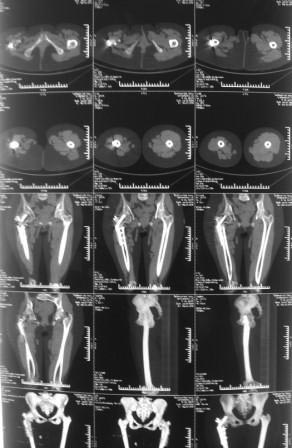

Ложный сустав бедра в подвертельной области

Уважаемые коллеги, обратилась девушка 1991г.р. 2 года назад оперирована в другой области по поводу диспластического коксоартроза

( похоже Мак Маррея, фиксация ЦИТО –Бакичарова), вот уже почти два года ходит с двумя костылями, наступать на ноги не может из-за боли, ногу активно поднять не может, активные движения в т/б суставе резко ограничены из-за боли, пассивные: 5/0/90гр, приведение - 20, отведение - 10гр, ротация-около -30, но болезненная. беспокоят боли в основном в обл ложного сустава, при движениях и пальпации в обл т/б сустава болей нет.

На Р-грамме, похоже, клинок пластини сломан, сращения нет.

В плане, учитывая возраст, эндопротезирование пока рано, может попробовать БИОС с рассверливанием, т.к мешающей контрактуры нет,и пусть походит, поживет, потом эндопротез.